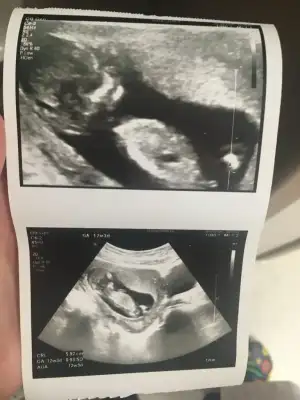

Aynen 12+3 suan minnoşumOo haftanda baya varmis masallah cinsiyeti gostereydi iyiydiSagligi yerinde olsunda isin sakasi kiyafet alalim die cinsiyet merakimiz